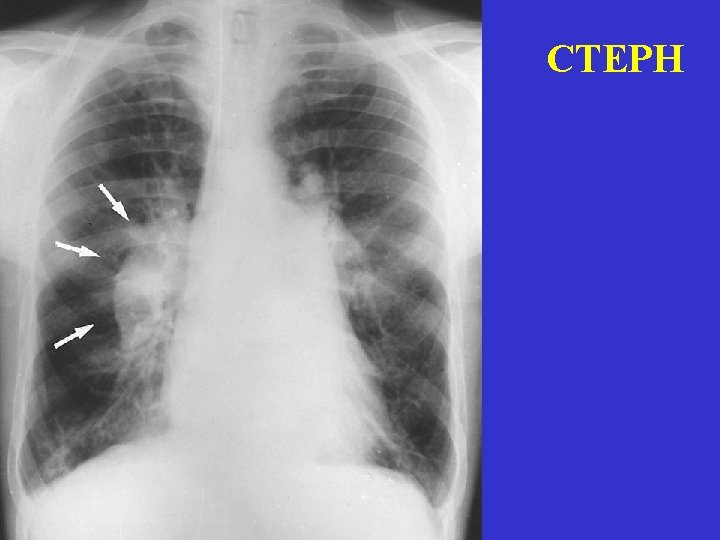

Chest X-ray and ECG X-ray Wide PA Elevated diaphragm Pleural fluid Wide RA vagy RV Infiltrate Atelectasia Local oligemia % 50 44 23 17 16 13 6 ECG ST depression Sinus tachycardia Negative T in V 2 -3 SV arrhythmia SI, QIII, negativ TIII RBBB P-pulmonale % 50 44 23 17 16 13 6

Chronic, reccurant PE (CTEPH) • • Reccurant episodes for months - years Progression of effort dyspnea Cyanosis Angina-like chest pain (decreased myocardial perfusion pressure) • Tachycardia, PII !, systolic ejection click • Death: progression of right heart failure Diff dg: COPD, CHF, hyperventilation sy